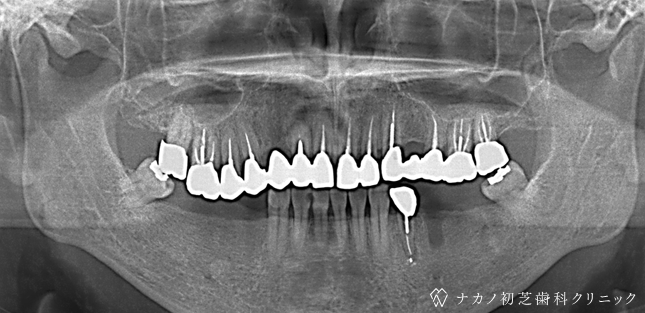

インプラント・13本 (60代女性)

BEFORE

AFTER

年齢 60代女性

治療内容 インプラント治療13本(骨造成の併用)

インプラント治療とは、歯を抜いた所にチタン製の人工歯根を埋入し、その上に歯を入れる方法です。骨を増やすことで、より審美的に治療が出来ました。費用 1本 400,000円(税込 440,000円)

リスク・副作用

腫れ・疼痛・違和感を感じるなどの症状を生じることがあります。